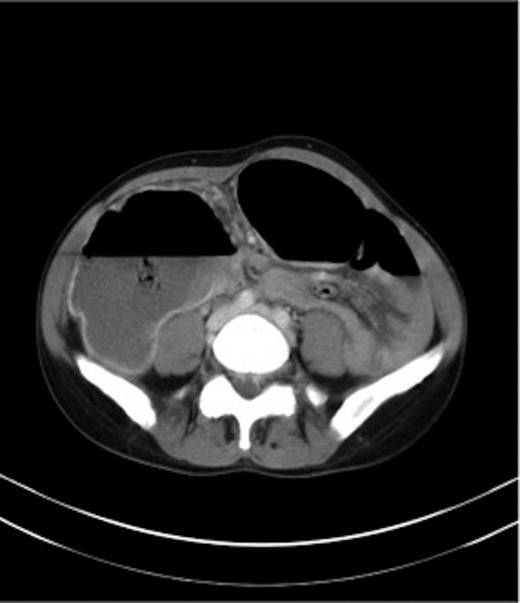

Haemoglobin was 14.9 g/dl and the white cell count (WCC) was 9 × 109/l. Other remarkable laboratory tests included a C-reactive protein (CRP) of 15 mg/l. Urinalysis was normal. The plain X-ray abdomen (AXR) (Fig. 1) revealed dilatation of a focal segment of large bowel with mildly dilated small bowel. Computed tomography (CT scan) of his abdomen reported that the gas-filled viscus is likely to represent the caecum (Fig. 2).

CT of the abdomen (Case 1) demonstrating the gas-filled caecum.